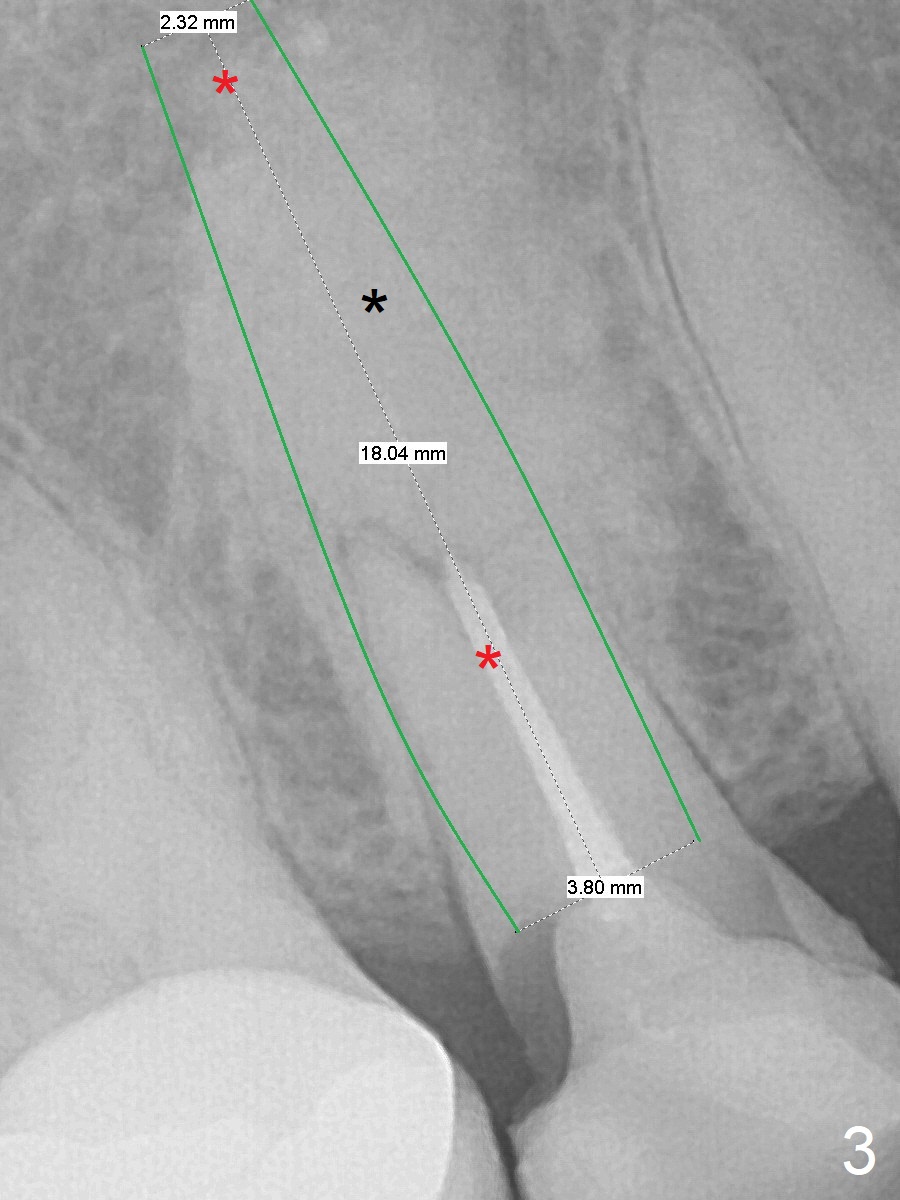

Two Point Engagement

A 41-year-old woman has multiple restorations. One of them, the tooth #4, has palatally subgingival fracture. There is sufficient bone height (Fig.2,3). The apex seems to have ben resected with periapical radiopaque lesion (Fig.3 black *, possible synthetic or bovine bone). To get two point engagement into the native bone (red *), the longest bone-level implant will be placed.